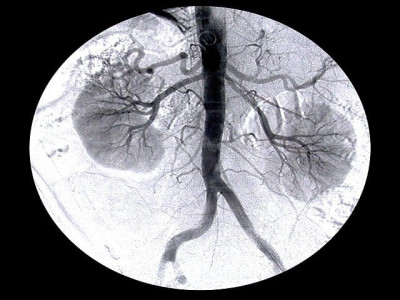

Religious talk: Scholars say organ transplant allowed in Islam

Different schools of Islamic thought represented at seminar